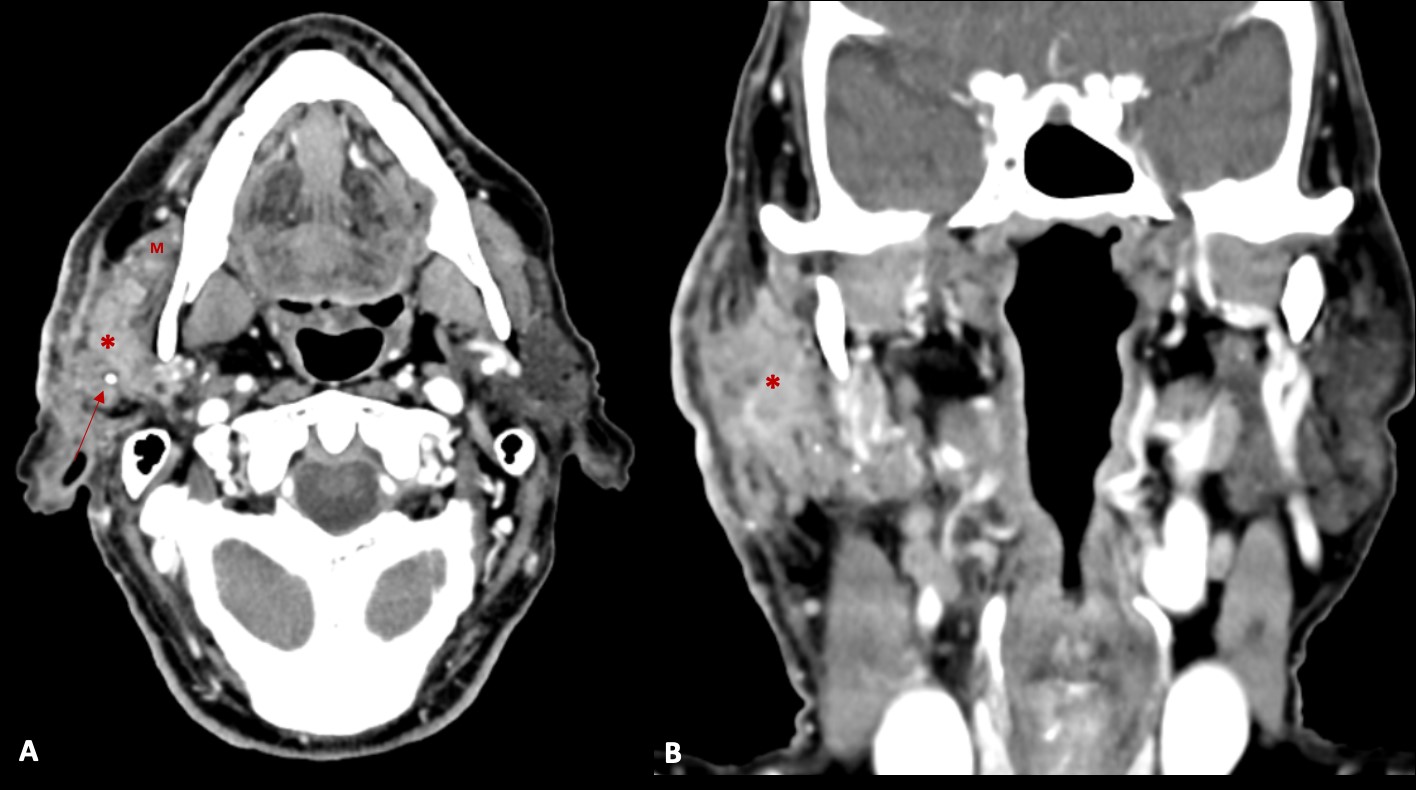

The patient denied a history of recent trauma. There was no evidence of facial paralysis or pain during palpation. A painless fibroelastic lymph node of about 1 cm was apparent at the right cervical level II. Facial/Cervical magnetic resonance imaging (MRI) and cervicothoracic computed tomography (CT) were performed, showing a diffuse infiltrative process of the right parotid gland, mimicking an inflammatory process (Fig. 2 and 3). The lesion showed a low signal on T1 and a heterogeneous signal on T2-weighted images, with heterogeneous post-contrast enhancement.

Figure 2: Contrast enhanced axial (A) and coronal (B) CT images, demonstrating an infiltrative mass (*) in the right parotid gland (in both superficial and deep lobes), that infiltrates the surrounding fat planes and skin, and invades the right masseter muscle (M). Some calcifications (arrow) are also present.